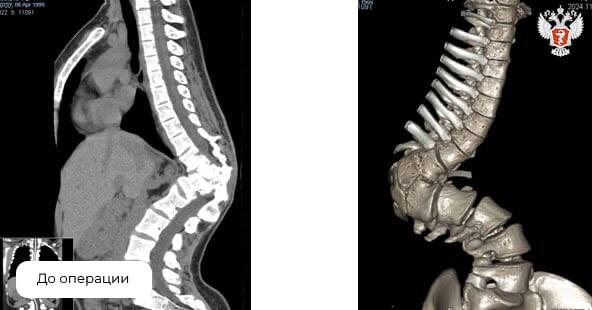

Деформация (горб в грудном отделе и сколиоз 72 градуса) развилась на фоне врожденной патологии позвоночника — у девушки был неправильно сформирован один позвонок на уровне грудного отдела.

Специалисты провели тщательное обследование и спланировали многоэтапное оперативное лечение:

• Сначала девушке установили аппарат внешней фиксации — уникальная разработка нейрохирургов медучреждения, с целью исправления деформации позвоночника;

• Затем удалили деформированный полупозвонок и провели дополнительную коррекцию;

• В ходе последней операции врачи зафиксировали позвоночник внутренней конструкцией для пожизненной стабилизации.